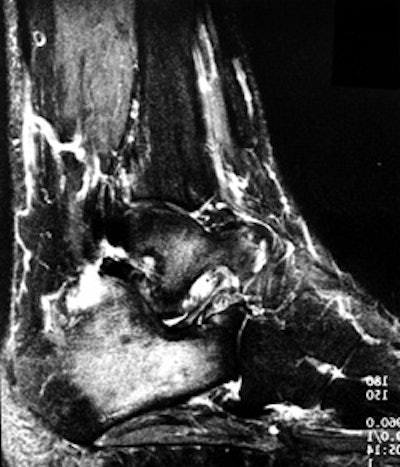

In 96 patients evaluated for arthritis pain, 218 joints were injected (figure 1).

FIGURE 1. (A) Lateral radiograph of a patient with hindfoot pain and the suggestion of subtalar arthrosis.

(B) Sagittal fat-suppressed MR image showing posterior facet arthrosis of the subtalar joint and edema within the sinus tarsi.

(C) The patient undergoing a series of injections with contrast seen in the ankle and sinus tarsi. The ankle injection did not relieve symptoms, the sinus tarsi injection relieved 75% of pain.

(D) Lateral radiograph 10 months after talo-calcaneal fusion and excision of the sinus tarsi contents with a reported 80% reduction in pain.

All joints were injected successfully. Based upon the degree of pain relief from injection, 22 patients were offered surgical treatment and 18 people chose surgical treatment. There were 7 painful ankles and 11 painful feet in 18 patients that had surgical treatment. All of the painful small joints of the foot had arthrodesis, 3 of the painful ankles had arthrodesis, 2 ankles had synovectomy and 2 had replacement arthroplasty. Ten of 11 patients with foot arthrodesis had pain relief similar to that of the injection and 1 patient had approximately 50% pain relief.

The ability to limit the number of joints fused by assessing pain relief from a series of preoperative image-guided arthrograms was also important. All patients have a minimum of 9 months follow-up since surgery. Five of 7 ankle pain patients had relief similar to the injection; one ankle arthroplasty and one arthrodesis patient had 50% improvement, none were worse following surgery. All surgical pathology specimens from the arthrodesis sites demonstrated the pathologic tissue changes of chronic synovitis, degenerative joint disease (i.e., bone and cartilage degeneration), or both.